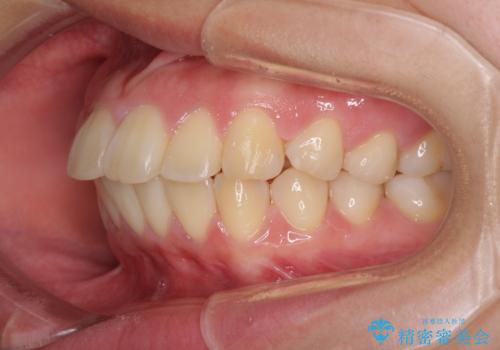

- 上下前歯を部分矯正したところ出っ歯になってしまったとのことで来院された患者様です。

上下左右第一小臼歯4本を抜歯して、積極的に口元を引っ込めるよう、ワイヤー装置にて矯正治療を行うこととしました。